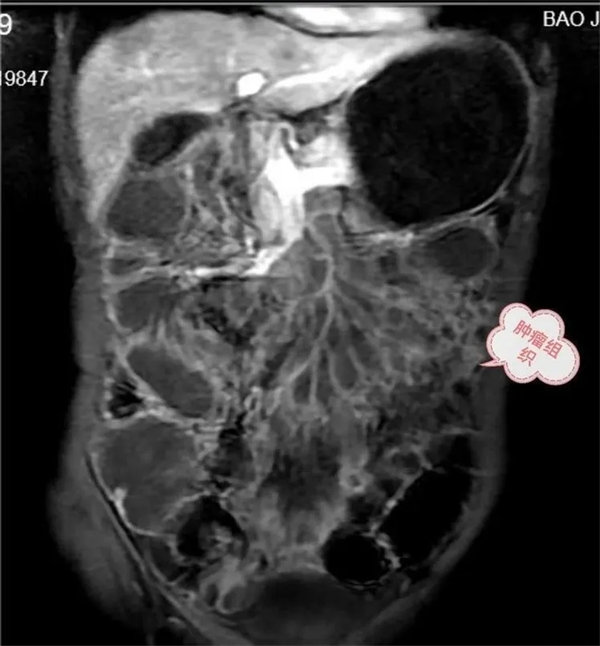

圖1,胃,小腸,結腸充盈顯示良好,局部小腸壁增厚,腸系膜病變組織包繞腸系膜動脈及分支血管塑形生長呈等T1,等T2信號腫塊。

圖2,動脈期,病灶無明顯強化,邊緣輕度強化。

圖3:延遲期,顯示腸系膜根部病變逐漸輕度強化。胃,結腸充盈顯示良好,腸壁強化,未見異常。